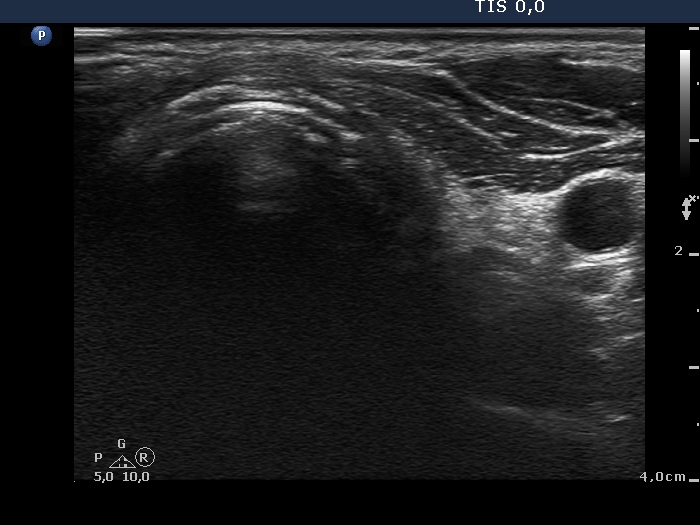

Five weeks after surgery (third row of images)

Ultrasonography. A moderately hypoechogenic mass with discrete circumscribed areas replaced the resected thyroid.

Taking the location and the morphology of the tumor into account we advised radioiodine therapy.